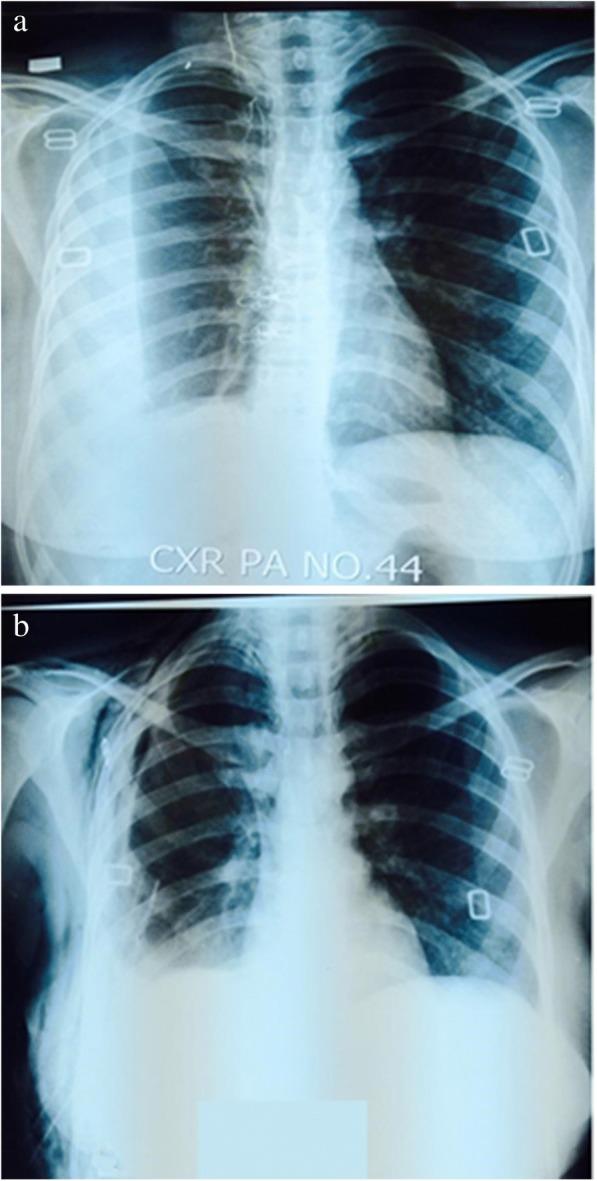

RESULTS

Out of 160 patients, 108 (67.50%) were male and 52 (32.5%) were female with mean age 25.37 years (range 16 to 70 years). Out of total, 102 (63.7%) had tuberculous empyema, while pleural biopsy of 58 (36.3%) patients was suggestive of non-tuberculous empyema. Final evolution through chest x-ray revealed complete resolution in 92 (57.5%), partial resolution in 58 (36.25%) patients. 9 (5.6%) developed persistent air leak while 1 (0.6%) patient expired due to urosepsis.

在 160 名患者中,108 名(67.50%)为男性,52 名(32.5%)为女性,平均年龄 25.37 岁(16-70 岁)。在所有患者中,102 例(63.7%)为结核性脓胸,58 例(36.3%)患者的胸腔活检提示为非结核性脓胸。通过胸部 X 射线最终演变显示 92 例(57.5%)完全缓解,58 例(36.25%)部分缓解。9 例(5.6%)发生持续的气胸,1 例(0.6%)因尿路感染死亡。